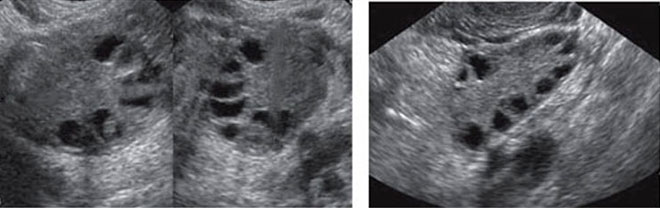

Если при исследовании УЗИ обнаружены 8-10 фолликулов, это говорит о признаках мультифолликулярных яичников. Но в большинстве своем это считается вариантом нормы. Периодически с подобным может столкнуться каждая четвертая здоровая женщина. В норме в течении цикла развивается до 7 фолликулов. Развитие же большего количества фолликулов может произойти однократно или наблюдаться в течении каждого цикла

После выхода из фолликула яйцеклетка живет около 2-х дней, если в этот период оплодотворение не произошло она погибает. Желтое тело также разрушается, что становится толчком к началу менструации. До овуляции обычно определяются доминантные фолликулы (1-2) и несколько антральных. Но если их значительно больше (8-10), то УЗИ выявляет мультифолликулярные яичники.